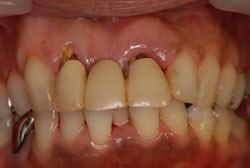

症例1

治療前

治療後

主訴 左上小臼歯から大臼歯部にかけて、脱離・歯冠崩壊、及び欠損があり、左奥では物が噛めない。

まだ年齢も50代と若く、義歯は煩わしく嫌であるという訴えがあり、左上5番・6番にインプラントを2本埋入する計画を立案。

副鼻腔までの距離がわずかしかないので、ソケットリフトと、骨の緻密化を計る為に、C・C・Wドリリング法を併用。

オぺから仮歯装着まで3ヶ月を要し、4ヶ月未満の治療期間を経て最終補綴物ジルコニア2本を装着。

リスクとしては、ソケットリフト(骨造成)による一過性の副鼻腔炎が起きる可能性がある。まれに洞底膜が破れる可能性がある。

ただし、膜は約3週で再生するので、膜の回復を待ち、再オペを行う。

費用 116万(オペ・ソケットリフト・人工骨・採血による濃縮血小板生成・仮歯・最終補綴物まで含む)